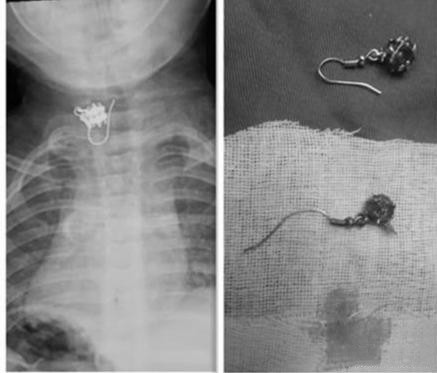

近段时间,某医院的医生将一个耳钉扔在铁盘里时,在场所有人都松了一口气。原来在11个小时以前,一个15月大的宝宝就把这个耳钉吃了。当时孩子的妈妈手中的事情还没忙完,等妈妈回头的时候,宝宝刚刚抓在手中的耳钉已经没有了。

妈妈意识到宝宝可能把耳钉吞进肚子里了,全家人想尽了各种的办法,但并没有作用。家人赶紧把孩子送到了医院,医生表示,耳钉卡在了孩子食道生理第二狭窄处,邻近气管和大动脉。如果再晚一步,就有可能扎破孩子的食道,威胁气管和主动脉。其实,类似孩子不小心吞下异物意外的报道屡见不鲜。